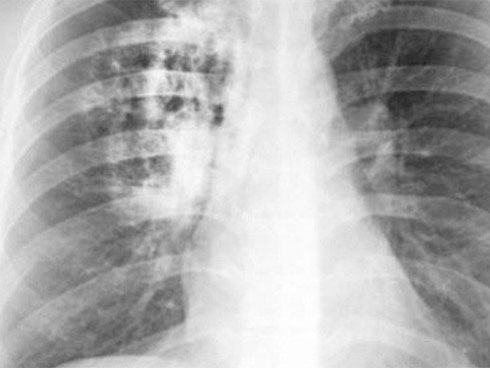

Tại Việt Nam, đa phần bệnh nhân được phát hiện khi đã ở giai đoạn muộn, chỉ 10-20% được chẩn đoán ở giai đoạn sớm. Ảnh minh hoạ: Internet

Tại Việt Nam, đa phần bệnh nhân được phát hiện khi đã ở giai đoạn muộn, chỉ 10-20% được chẩn đoán ở giai đoạn sớm. Theo các BS chuyên khoa ung thư ở giai đoạn sớm bệnh có những triệu chứng rất nghèo nàn, bệnh nhân dễ nhầm lẫn với những bệnh lý về đường hô hấp khác.

Khoảng 80% bệnh nhân ung thư phổi có triệu chứng ho khan, ho kéo dài, khó lý giải nguyên nhân hoặc ho có đờm trắng/nhiều đờm, có khi có bội nhiễm.

Tiến sĩ Đinh Văn Lượng, Phó giám đốc Trung tâm Ung thư Phổi Quốc gia, cũng cho biết khi bệnh nhân có các triệu chứng như ho, khó thở, ho ra máu, ho đờm… thường không còn ở giai đoạn sớm.